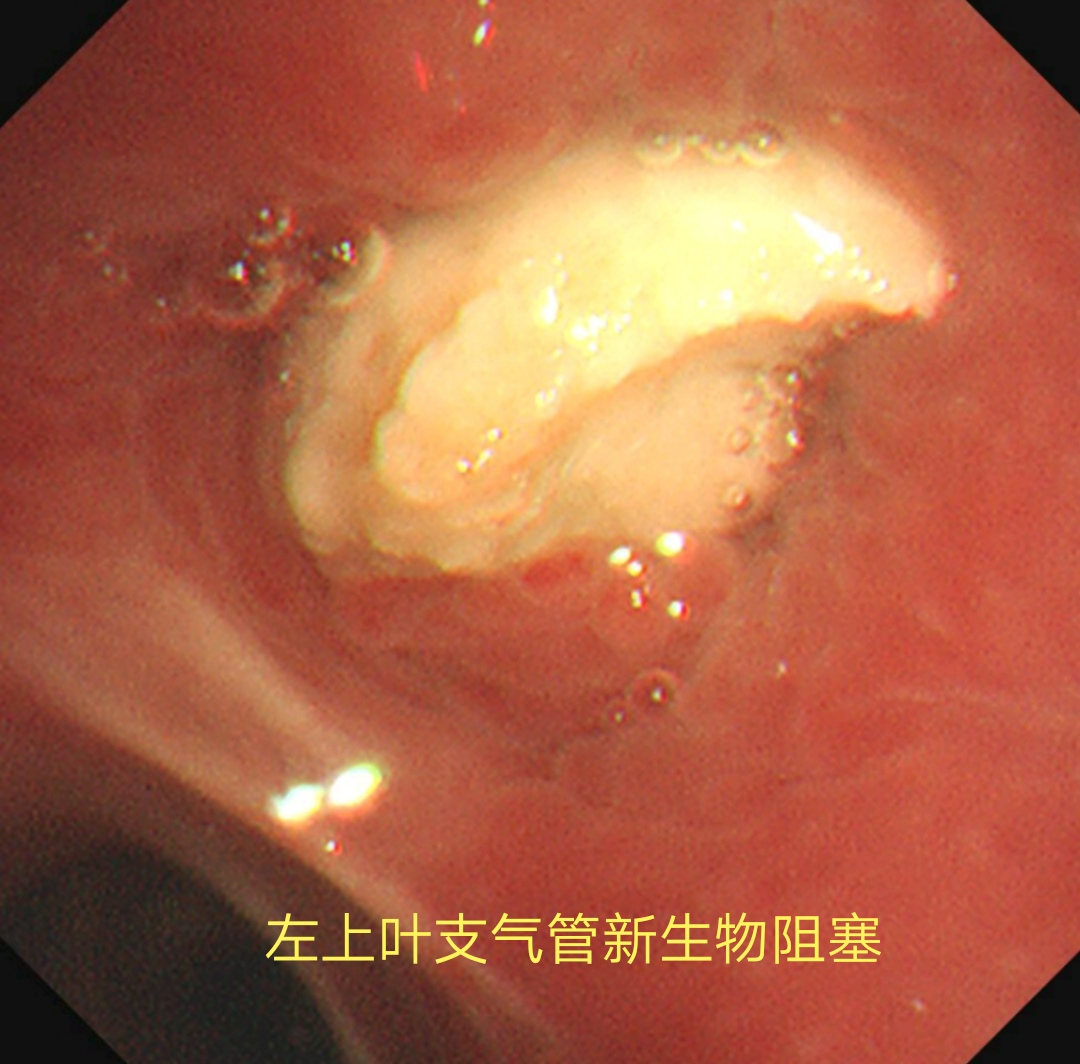

入住医院呼吸与危重症医学科后,经呼吸系疑难病多学科专家会诊,决定为马某行无痛支气管镜检查,以进一步明确病因。支气管镜见左上叶支气管口有新生物,坏死物附着并阻塞管腔,遂行病变活检,以明确诊断。出人意料的是活检病理中看到了少量异物成分。